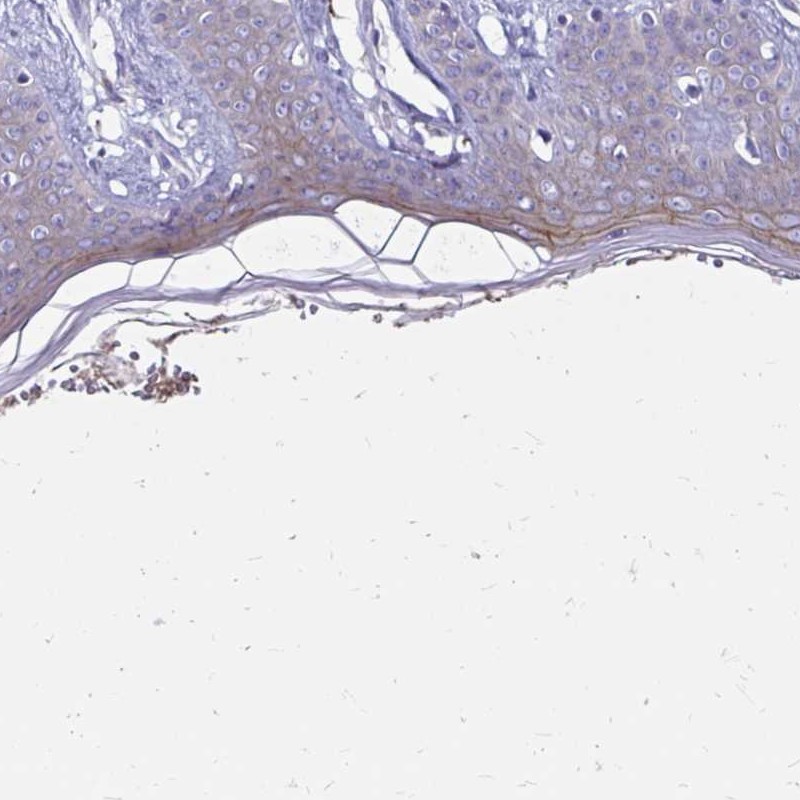

Immunohistochemistry analysis in human skin and skeletal muscle tissues using Anti-EVPL antibody. Corresponding EVPL RNA-seq data are presented for the same tissues.